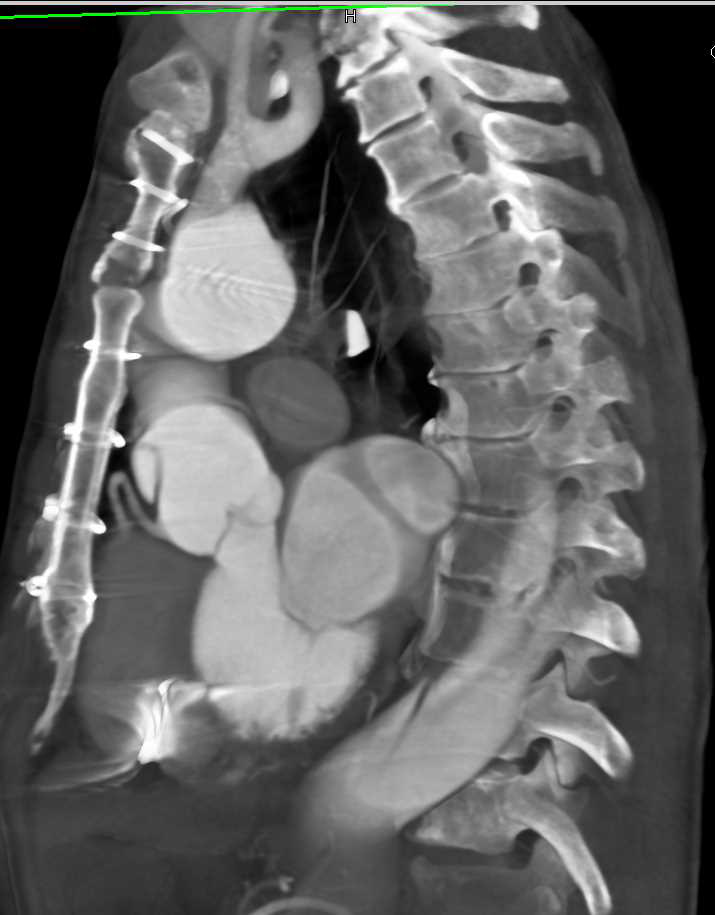

Left Popliteal Artery Occlusion Following Trauma with Dual Energy